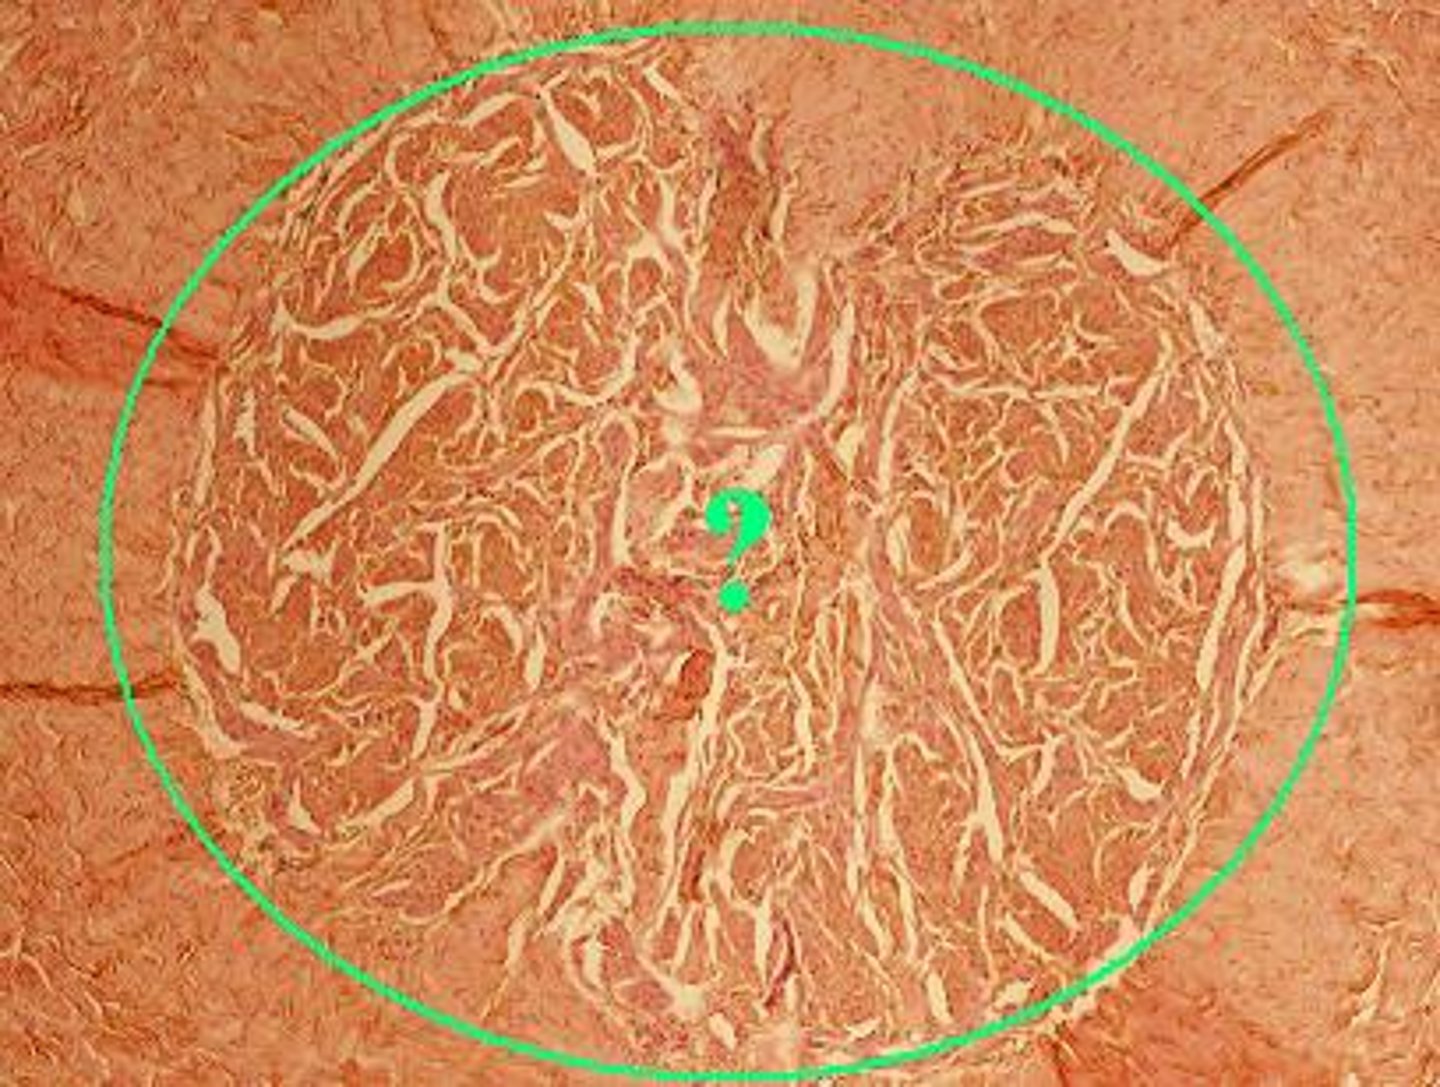

glomerulus

What portion of the nephron is the site of the filtration of blood plasma and the formation of urinary filtrate?

Where in the nephron does filtration take place?

Identify the indicated region of the nephron.

Identify the indicated structure in the kidney.